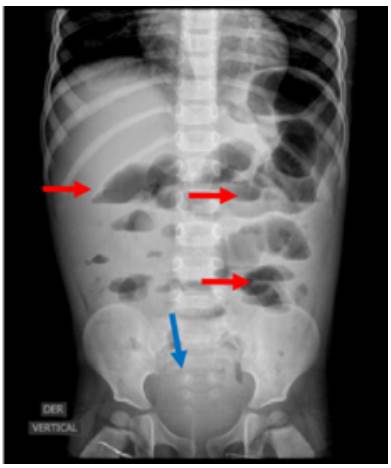

The findings during surgery were severe adhesion syndrome, contained intestinal perforation of 5 mm in the anti-mesenteric border at 1 m from the Treitz angle, acute perforated stump appendicitis based on generalized peritonitis (Figure 2), and unperforated Meckel's diverticulum at 50 cm of the ileocecal valve (Figure 3). Based on these findings, laparotomy, appendectomy, generalized peritonitis drainage with cavity lavage, adhesion release, diverticulectomy, enterorrhaphy, and skin closure were performed.